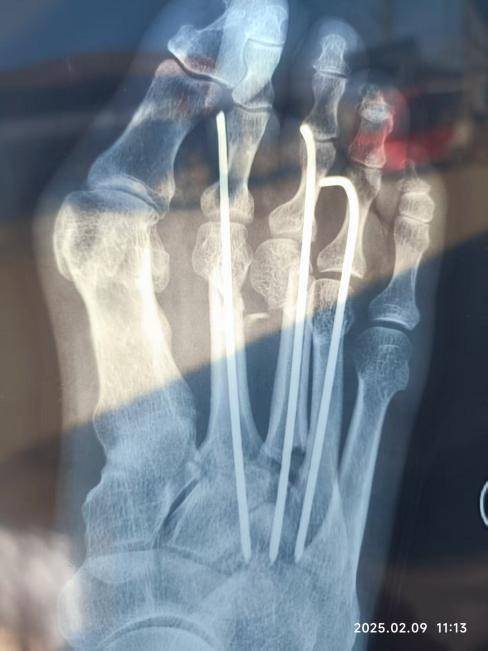

在省附属医院,医生的诊断结果如同晴天霹雳,让张玉祥老人一家陷入绝望。他被诊断出四节脊椎骨折,锁骨骨折,三根肋骨骨折,左腿开放性骨折,右脚三根脚趾骨折,其中一根更是折成了两截。短短的十六天住院治疗,却未能让他恢复如初。出院后,老人彻底失去了劳动能力,只能在家中卧床休养。

更令人痛心的是,经此一劫,张玉祥老人的身体留下了永久的残疾。至今,他的右脚四根脚趾依然无法回弯,走路行动受阻,全身多处伤残,对他的生活和身心造成了难以磨灭的创伤。曾经勤劳的双手再也无法耕作,曾经稳健的双腿也已步履蹒跚。